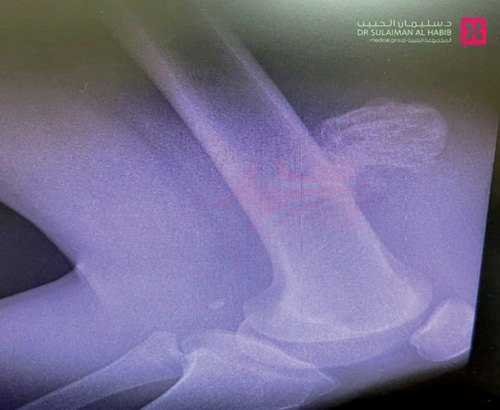

وأوضح د. العماري أن المريض فور وصوله إلى المستشفى، خضع لكشف سريري أظهَرَ وجود ورم غضروفي عظمي في الفخذ أعلى الركبة، ومن ثم أجريت له مجموعة من الفحوصات الطبية الدقيقة من بينها التصوير بالأشعة المقطعية والرنين المغناطيسي، وبعد دراسة الحالة على ضوء نتائج الفحوصات خلص الفريق الطبي إلى أن الوضع يقتضي التدخل الجراحي، وبعد اتخاذ الترتيبات والتجهيزات اللازمة، خضع المريض لعملية تم فيها استئصال الورم الذي بلغ وزنه «378» جرامًا، بشكل كامل وصولاً إلى العظم السليم، وجرت الجراحة التي استمرت لنحو ساعة ونصف الساعة بسلاسة؛ على الرغم من أن موضع العملية من الناحية التشريحية يتسم بتعقيدات عالية. وأضاف د. العماري أن تَمَيُّز الفريق الطبي وكفاءته وراء نجاح هذه العملية المعقدة، التي أنهت معاناة الشاب مع الآلام المستمرة، وأعادت له قدرته على الحركة وممارسة حياته بصورة طبيعية، وجنّبته - بفضل الله- مضاعفات صحية أكثر حدة، كتزايد الضغط على الأوردة والشرايين المغذية للطرف السفلي، وبالتالي تراجع قدرة المريض على الحركة، وزيادة الآلام.